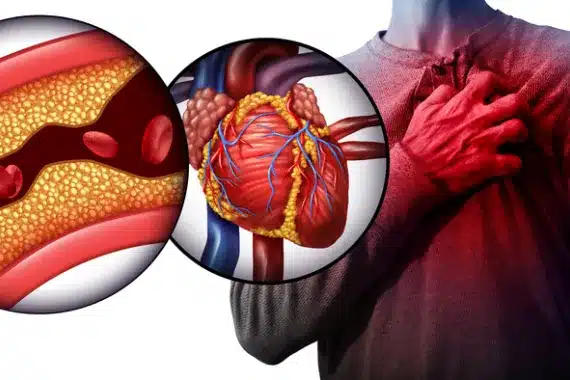

Η στεφανιαία νόσος (CHD) εμφανίζεται όταν η παροχή αίματος στον καρδιακό σας μυ εμποδίζεται ή διακόπτεται από τη συσσώρευση λιπαρών ουσιών (αθήρωμα) στις στεφανιαίες αρτηρίες. Οι στεφανιαίες αρτηρίες είναι τα κύρια αιμοφόρα αγγεία που τροφοδοτούν την καρδιά σας με αίμα.

Εάν οι στεφανιαίες αρτηρίες σας στενέψουν λόγω συσσώρευσης αθηρώματος, η παροχή αίματος στον καρδιακό σας μυ θα περιοριστεί. Αυτό μπορεί να προκαλέσει στηθάγχη (πόνους στο στήθος). Εάν μια στεφανιαία αρτηρία αποφραχθεί εντελώς, μπορεί να προκαλέσει καρδιακή προσβολή. Αυτό είναι επείγουσα ιατρική κατάσταση.